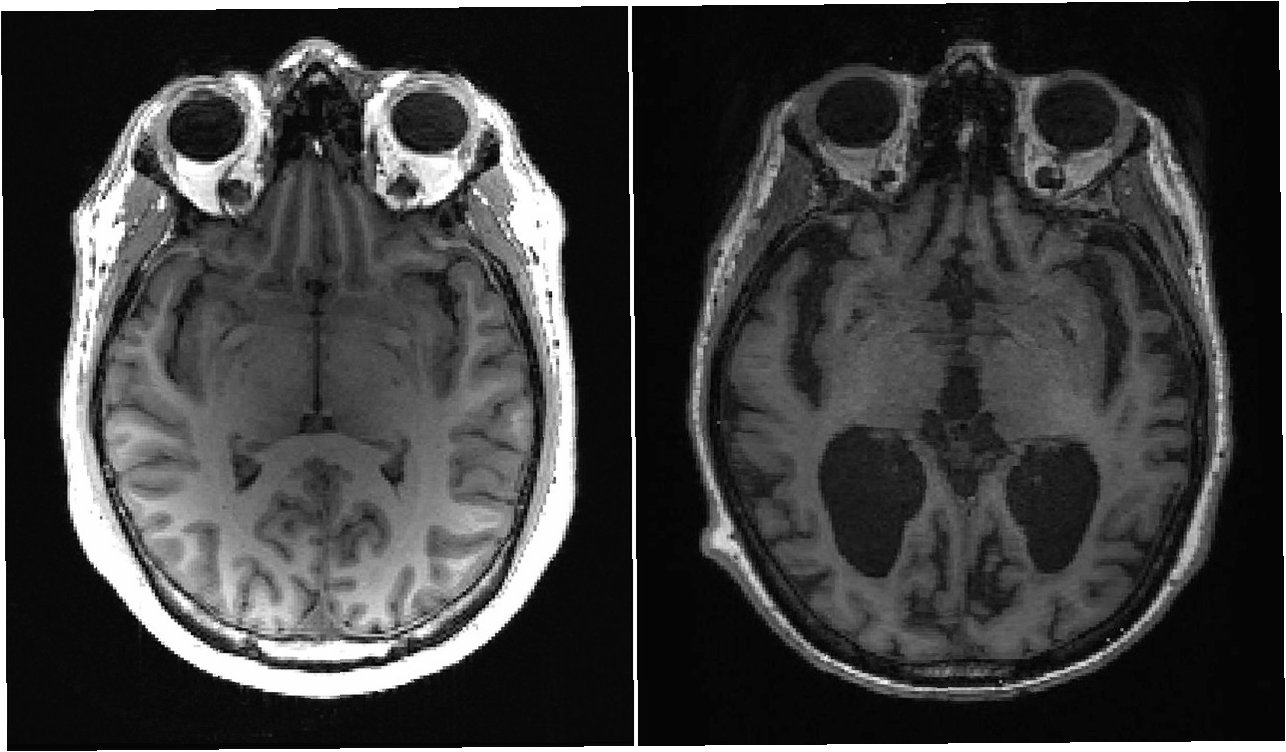

AI 기술은 치매 연구에서 핵심적인 역할을 수행합니다. AI는 방대한 양의 데이터를 빠르고 정확하게 분석하고, 인간의 눈으로는 발견하기 어려운 패턴을 찾아냅니다. 뇌 영상 데이터 분석을 통해, AI는 치매 환자의 뇌 구조 및 기능의 변화를 감지하고, 질병의 진행 단계를 예측할 수 있습니다. 유전자 정보 분석을 통해, AI는 치매 발병 위험을 높이는 유전자 변이를 식별하고, 개인별 맞춤형 치료법 개발의 기반을 마련합니다. 또한, AI는 임상 데이터를 분석하여 환자의 상태를 정확하게 평가하고, 치료 효과를 예측하는 데 도움을 줍니다. 이러한 AI 기술의 활용은 치매 연구의 효율성을 높이고, 새로운 치료법 개발을 가속화하는 데 기여합니다. AI는 치매 연구의 혁신을 이끄는 핵심 동력이며, 미래에는 더욱 발전된 기술을 통해 치매 정복에 기여할 것으로 기대됩니다.